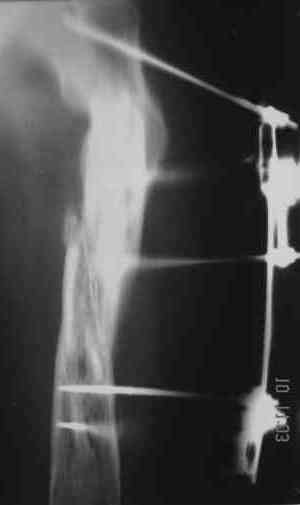

Надо делать чрескожную подвертельную остеотомию, чтобы получился открытый клин. Проблемы будут и с формированием канала, надо развертки типа наших. Был как-то похожий случай, сделали одномоментно, сняли аппарат 5-месячый на столе, заштифтовали с подвертельной остеотомией (в приложении).

Можно все коррекции сделать и в аппарате, и потом заштифтовать, тогда останется только одна проблема формирования канала.